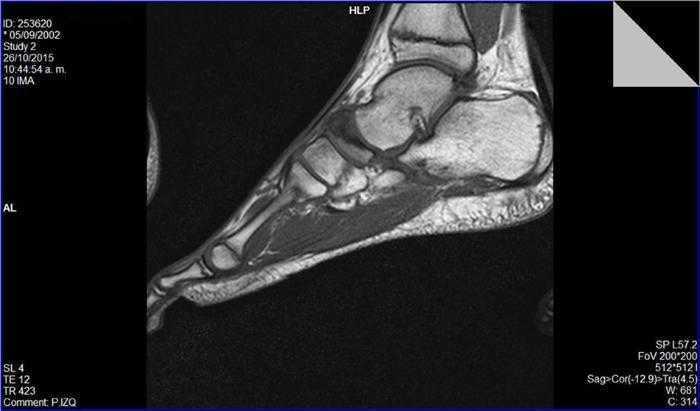

Se realizaron radiografías en proyecciones anteroposterior y oblicua, que mostraron un primer radio corto y esclerosis del escafoides tarsiano con aplanamiento anteroposterior, y un acuñamiento del aspecto lateral dando una morfología en forma de «coma» (Figura 1). En la proyección lateral se observó un trazo de fractura de 45° de inclinación. Con estos hallazgos se suspendió la actividad deportiva y se mantuvo en descarga durante 4 semanas. Se realizaron una resonancia magnética y una tomografía computarizada. La tomografía mostró un trazo de fractura en el escafoides izquierdo y signos de lesión osteocondral (Figura 2). La resonancia mostró un extenso edema intraóseo del escafoides tarsiano, aplanamiento del aspecto lateral, un área con marcada alteración de señal sugestivo de osteonecrosis y una imagen lineal de morfología cóncava que afectaba el aspecto dorsal y lateral del escafoides (Figura 3).

Figura 1. Radiografía anteroposterior: alteración en la morfología del escafoides tarsiano en forma de «coma». Primer metatarsiano corto.